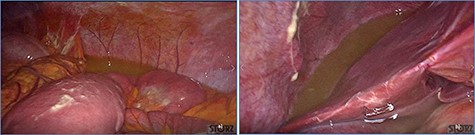

fluid collection in the peritoneal cavity. Subsequent CT confirmed the presence of diffuse fluid collection in the peritoneal cavity (Fig. 1) but no free air, with distention, bundling and thickening of some small bowel in the left quadrant (Fig. 2). The patient was therefore admitted for supporting therapy (intravenous fluids and antibiotics) with the suspicion of cocaine-induced small bowel ischemia. Twelve hours later, signs and symptoms of diffuse peritonitis developed: worsening diffuse abdominal pain with rebound guarding at examination, a significant increase in WBCs count (16.15 × 103/μl) and neutrophilia (88%), lengthening of coagulation times (INR: 1.68; aPTT: 33.0 s) and increase in fibrinogen (430 mg/dl) and D-Dimer (2275 ng/ml). Therefore, urgent surgical exploration of the abdomen through a three-port open laparoscopic approach was performed, confirming the presence of 1200 ml of exudative fluid and fibrin clots (Fig. 3). Several adhesions between greater omentum, abdominal wall and small bowel underwent blunt dissection. Thorough exploration of the small bowel revealed two ischemic segments located at about 50 and 100 cm from the Treitz ligament (Fig. 4). The large bowel appeared normal. The existence of non-visible gastro-duodenal perforations was ruled out with the administration of 500 ml of saline with 20 ml of methylene blue through the nasogastric tube. An iv bolus of sodium heparin, 10 000 IU, was then administered, performing a 30-min peritoneal lavage with 5 l of saline solution at 37°C. After reaspiration of peritoneal lavage, a new complete exploration of the small bowel was performed, showing complete revascularization of the two ischemic small bowel segments (Fig. 5). Two tubular drainage tubes were placed in the left and right colic gutters. Culture examination of peritoneal exudate was positive for multi-sensitive Escherichia coli and Enterococcus, thus confirming bacterial translocation peritonitis. Postoperative therapy included the administration of iv piperacillin–tazobactam and subcutaneous low molecular weight heparin. Postoperative recovery was smooth, with oral feeding on the second postoperative day (POD), drainage removal on POD 3, complete bowel function restored on POD 4 and home discharge on POD 5. At 15- and 30-day-follow-up, the patient showed full recovery, being now followed by a specialized support structure for his drug abuse.

Diffuse exudative fluid and fibrin clots at laparoscopic exploration: (a) left upper quadrant and (b) right upper quadrant.